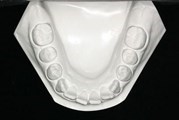

Dental Casts

right buccal frontal left buccal upper mandibular

Right Buccal View Frontal View Left Buccal View Maxillary View Mandibular View